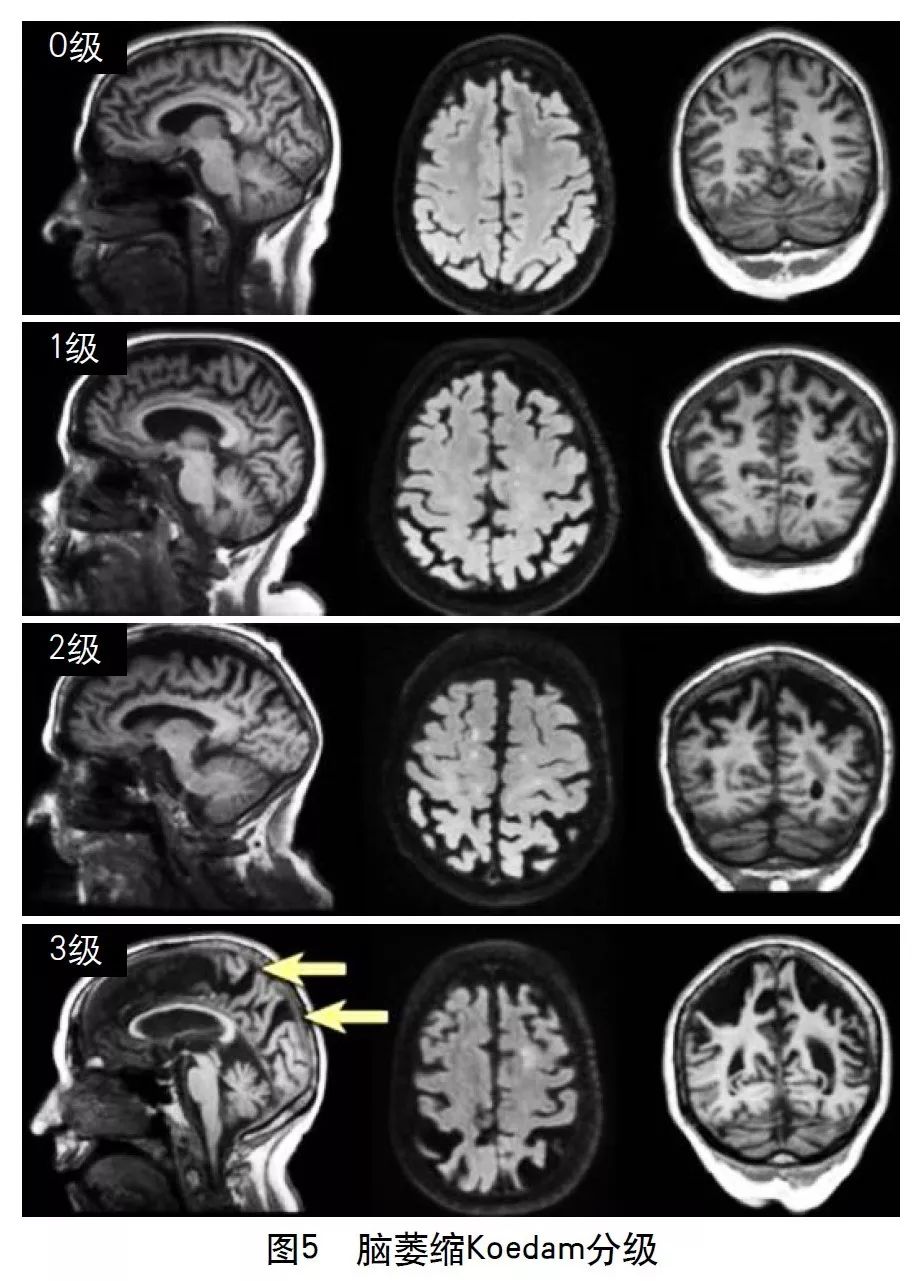

2013年的共识指南将脑萎缩定义为与特定的局灶性损伤,如脑外伤或脑梗死无关的脑容积减少。脑萎缩可以是广泛的或局部的(如特定的脑叶或海马等特定区域),可以是对称或不对称的,亦可以是组织选择性的(如发生在白质等某一特定组织层)。目前不同部位的脑萎缩有相应的诊断标准,全脑皮层萎缩分级用于评价全脑(图3);内侧颞叶萎缩分级主要评价颞叶内侧,重点是海马(图4);Koedam分级主要评价顶叶,尤其是扣带回和楔前叶(图5);Kipps/Davies分级主要评价额颞叶(图6)。推测脑组织减少是由脑沟(周围)和脑室(中心)的脑脊液空间相对于颅内容积扩大所引起的。